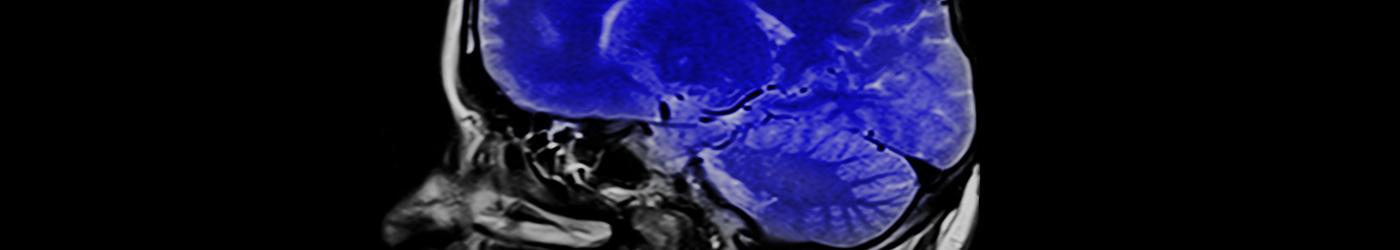

Nuestros neurocirujanos realizan tratamiento quirúrgico de determinadas patologías de los sistemas nerviosos central, periférico y vegetativo, incluyendo sus estructuras vasculares; los procesos patológicos que modifican la función o la actividad del sistema nervioso, incluyendo la hipófisis y el tratamiento quirúrgico del dolor.